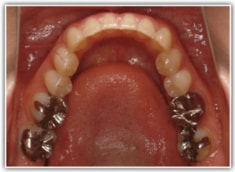

治療後(1年6ヶ月後)